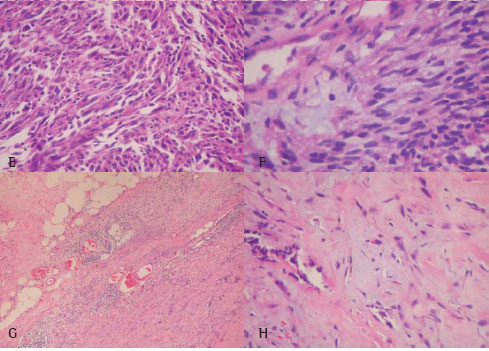

Departamento de Patologia do Hospital Pedro Ernesto (RJ). A reavaliação histológica dos subtipos foi realizada por dois patologistas de acordo com a classificação atual da Organização Mundial de Saúde. Nos casos em que a histologia revelou aspectos incomuns para mesotelioma tentou-se um diagnóstico diferencial. Duas categorias principais de diagnóstico histopatológico resultaram deste procedimento: 1) um padrão histológico típico para mesotelioma e 2) uma apresentação atípica. As dificuldades em se atingir um diagnóstico não foram nunca causadas pela pequena quantidade de tecido tumoral disponível, mas sim devido ao próprio quadro histológico. Na Figura 1 (painéis A a F) e na Figura 2 (painéis A a F) apresentam, respectivamente, exemplos de padrão histológico típico e atípico. Os dados fornecedores de informações quanto à epidemiologia e ao prognóstico foram coletados a partir do histórico dos casos e através de entrevistas. O tempo de sobrevida foi calculado a partir da data do diagnóstico.

Classificou-se como adenocarcinoma 5 dos 12 casos classificados como de padrão histológico atípico para mesotelioma e 6 dos 46 casos pertencentes à categoria típica. Entre estes 11 casos de adenocarcinoma, 7 foram positivos para CEA, 8 para Leu-M1 e 3 para calretinina. Após a exclusão dos casos de adenocarcinoma por IHQ, a determinação dos subtipos entre os casos de mesotelioma revelou 22 do tipo epitelial (Figura 1A, 1B), 12 do tipo bifásico (Figuras 2C, 2D), 5 do tipo sarcomatóide (Figuras 3E, 3F) e 1 do tipo desmoplásico.